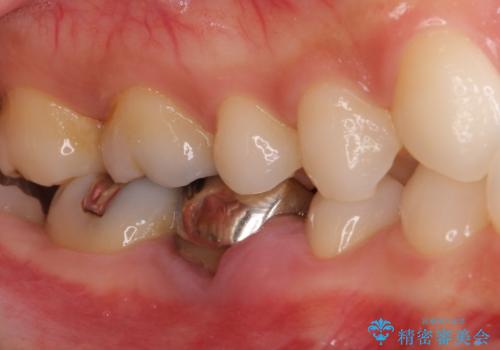

折れてしまった奥歯 下の奥歯のインプラント治療

- 近医で奥歯の抜歯が必要であると指摘され、インプラント治療を希望して来院された患者様です。

診察の結果、歯が破折しており抜歯が必要でした。